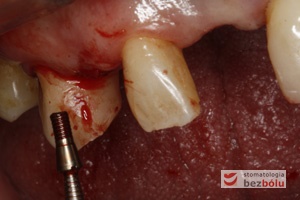

Wprowadzenie implantu do łoża - implant Ankylos wprowadzany ręcznie przy użyciu raczety

Wprowadzenie implantu do łoża – implant Ankylos wprowadzany ręcznie przy użyciu raczety

Wprowadzanie implantu w pozycji kła - ręczne wprowadzanie implantu daje możliwość kontroli torku i regulowania tempa implantacji

Wprowadzanie implantu w pozycji kła – ręczne wprowadzanie implantu daje możliwość kontroli torku i regulowania tempa implantacji